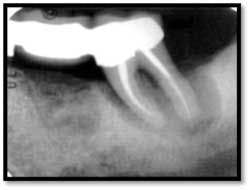

Pockets 4-9mm Class ll furcation involvement in both molars, possible endo abscess #3, (tooth is asymptomatic)

LR Pre TxPockets: 4-8mm

A full set of radiographs taken 13 months post therapy show bone fill in the deepest pockets, with generalized pocket reductions of up to 7mm.